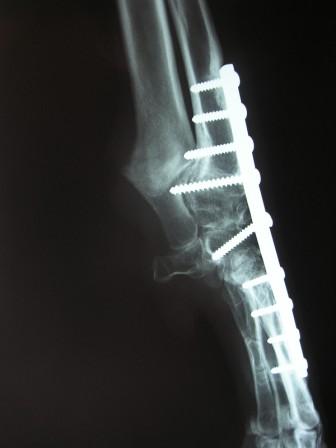

Ostéotomies Correctrices des Déformations Osseuses

Post opératoire